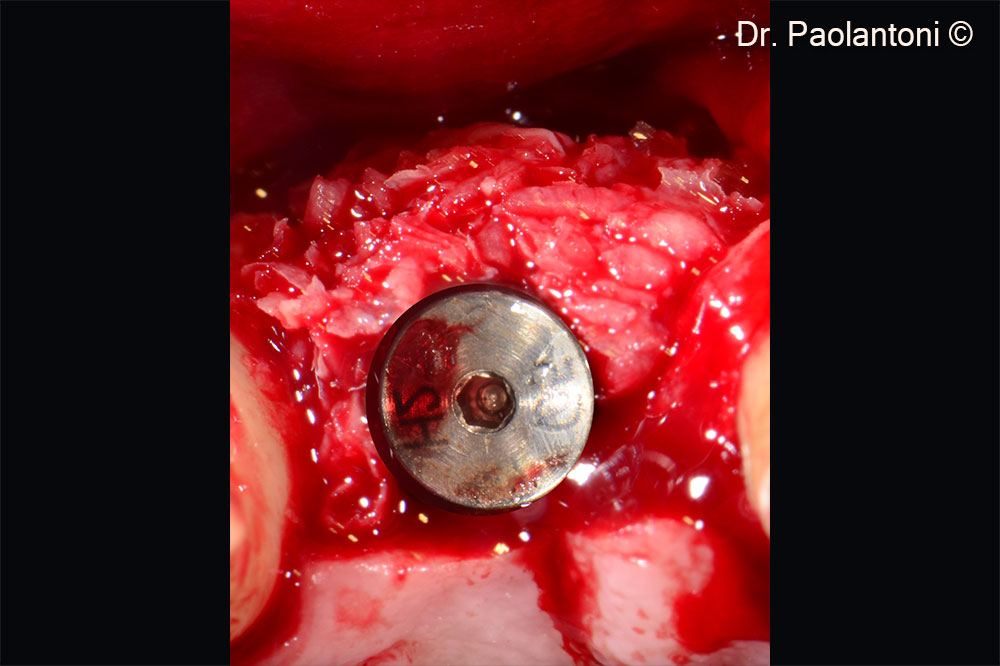

Gen-Os® is used in the buccal portion to fill the bone defect